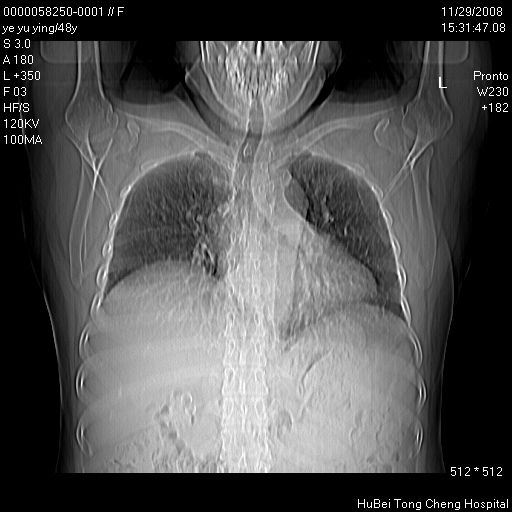

以下是引用zsl6918在2008-11-29 21:47:00的发言:[br]恶性肿瘤病史,转移瘤首先考虑。脂肪肝,胆囊结石。

以下是引用huenhao在2008-11-29 22:11:00的发言:[br]脂肪肝,胆囊结石。左肺病灶建议定期复查。

以下是引用liuyue在2008-11-30 5:44:00的发言:[br]1.左肺病变,首先考虑感染性病变,转移待排;建议治疗后复查。[br]2.肝脏密度普遍减低,考虑与化疗有关。[br]3.胆囊结石.